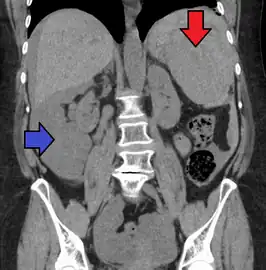

Image of abdomen shows ruptured spleen (and the perisplenic hematoma)

Traumatic rupture of the spleen on contrast enhanced axial CT (portal venous phase)

Splenic hematoma resulting in free abdominal blood

Splenic rupture is usually evaluated by FAST ultrasound of the abdomen.[3] Generally this is not specific to splenic injury; however, it is useful to determine the presence of free floating blood in the peritoneum.[3] A diagnostic peritoneal lavage, while not ideal, may be used to evaluate the presence of internal bleeding a person who is hemodynamically unstable.[4] The FAST exam typically serves to evaluate the need to perform a CT scan.[4] Computed tomography with IV contrast is the preferred imaging study as it can provide high quality images of the full peritoneal cavity.[3]